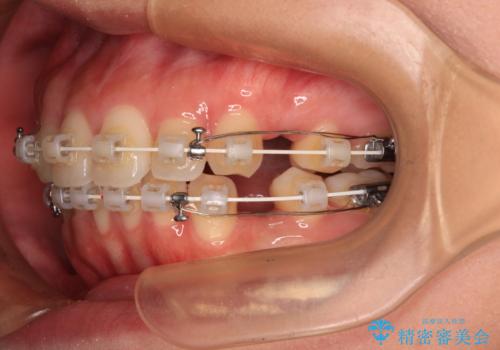

- 矯正装置

- 審美装置

- 全体的なデコボコと口元の突出感を改善したいとのことで来院された患者様です。

このままデコボコを整えるとさらに突出感が増すため、上下左右の第一小臼歯を抜歯し、ワイヤー装置にて矯正しました。